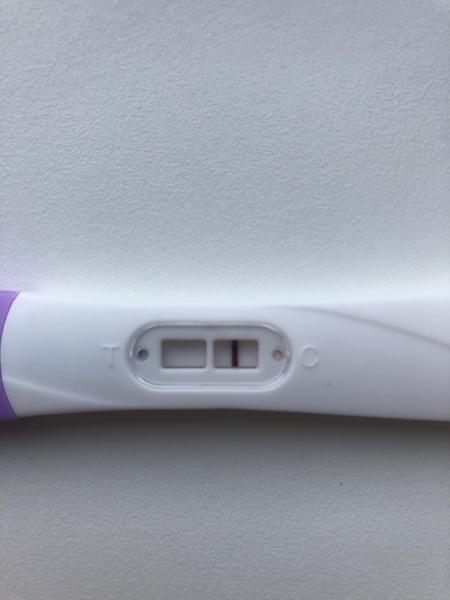

ahojte babule, mam taku otazku...mate skusenost ze pocas 3 dni vam nesilnela druha ciarka na teste ale bola rovnaka???ako duch????

@danikol dakujem, ona uz silnie, to je par tyzdnov dozadu 🙂 uz mam menej nez tyzden do kontroly u dr

Ahojte baby potrebujem radu dnes som 9-10dpo, od včera mi je zle na žalúdku, vracala som, aj dnes mi je tak isto, tak je mi cudne... A test som si spravila až teraz poobede a nič tam špeciálne nevidím vy áno? Viem ze je to skoro, ale nedalo mi tak som si test spravila a zatiaľ tam nič nie je iba taky ako duch alebo len kanálik 🤔 neviem ťažko povedať..

@tinadeville no tebe to vidno pekne, ja som to mala takto isto voľným okom to lepšie bolo vidno